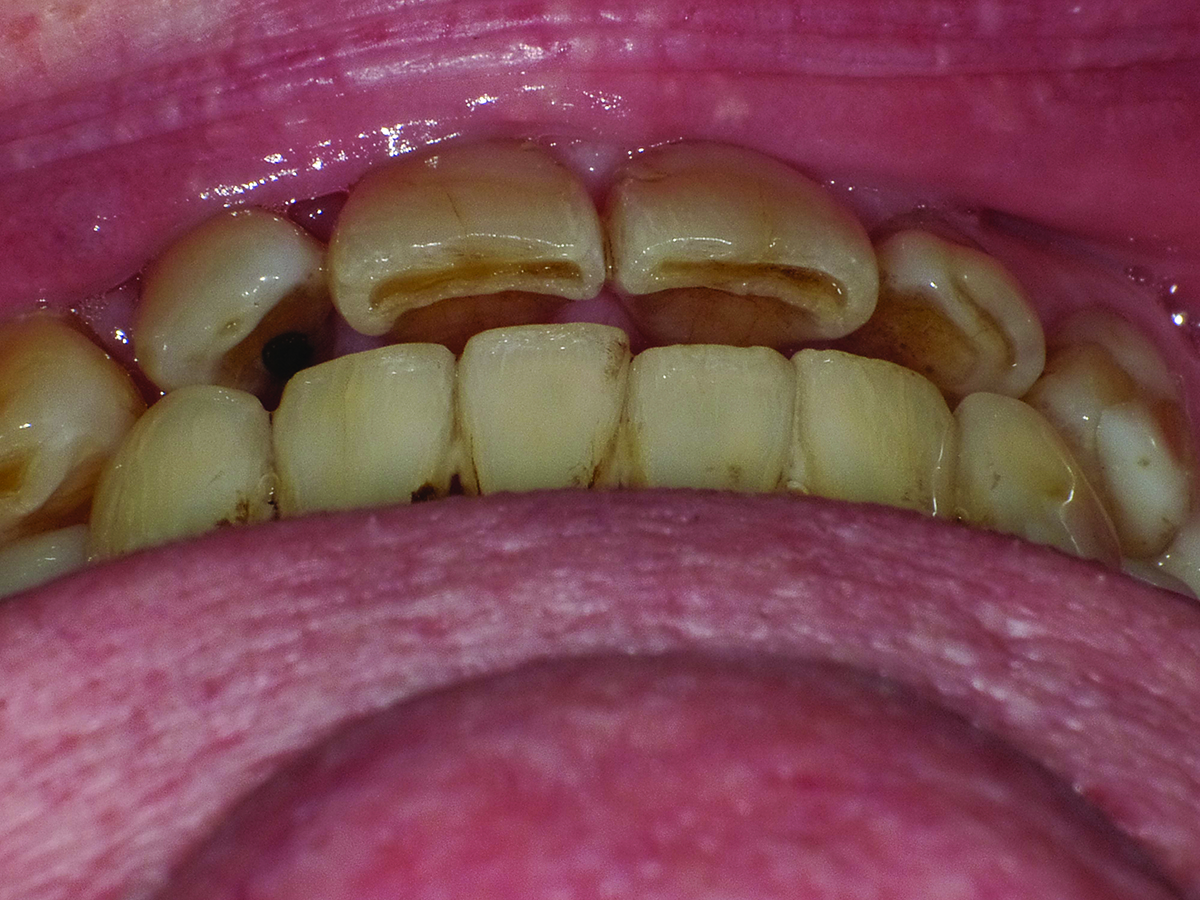

Close-up view of patient’s dentition in 2009.

Figure 1

Close-up view of patient’s dentition in 2017 showing increased facial and buccal erosion over the past 8 years.

Figure 2

Extreme changes in an adult dentition can occur rapidly when multiple risk factors are combined. In the case presented, the male patient’s dentition changed dramatically over an 8-year period due in large part to gastroesophageal reflux disease (GERD) and daytime clenching. Significant generalized enamel and dentin loss had occurred, and the patient’s maxillary lateral teeth had shifted despite a healthy periodontium.

Biomechanical: Significant tooth structure loss had occurred between 2009 and 2017 (Figure 1 through Figure 3). Severe attrition had occurred on the anterior teeth, especially tooth No. 11. Severe erosion and abrasion were present on teeth Nos. 11, 18, 20, 21, 28, 29, 31, and 32 (Fig-

ure 4). The patient had generalized sensitivity, and tooth No. 18 was painful due to deep erosion, which approached the pulp chamber. Teeth Nos. 7 and 10 had moved out of position and rotated (Figure 5). The progression of erosion over the 8-year period could also be seen radiographically and was especially noticeable on tooth